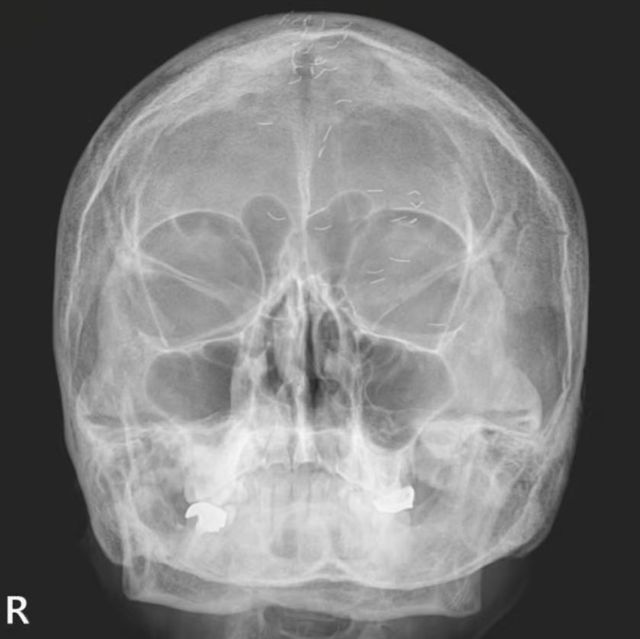

60대 한국 여성의 머릿속에 수많은 이물질이 흩어져 있는 엑스레이 사진이 공개돼 화제를 모았다. 얼핏 보면 기생충처럼 보이는 이물질의 정체는 한방 치료법 중 하나인 금침이었다.

가정의학과 전문의 양성관은 지난 8일 자신의 SNS에 ‘한국형 진료’라는 제목과 함께 해당 엑스레이 사진을 공개했다.

양 의사는 “60대 여성 환자의 엑스레이를 촬영했더니 1cm 크기의 이물질들이 다수 발견됐다”며 “기생충인가? 전기칩인가? 외국이었다면 특이한 사례로 의학 저널에 보고됐을 것”이라고 말했다. 하지만 한국 의사들은 이를 보자마자 금침 치료의 흔적임을 알아볼 수 있다고 설명했다.

금침은 ‘금실매선요법’이라고도 불리며, 가늘게 절단한 순금을 통증 부위에 삽입하는 치료법이다. 금이 해당 부위를 지속적으로 자극해 통증 완화 효과를 유도하는 것으로 알려져 있다. 주로 무릎이나 허리 등에 시술되지만, 이번 사례에서는 머리에서 발견돼 더욱 눈길을 끌었다.

이 환자는 오랜 기간 금침 치료를 받아왔으며, 양 의사가 내린 최종 진단명은 ‘긴장성 두통’이었다.

양 의사는 “머리 중앙이 자주 아파 침 치료를 받았고, 신경과에서 MRI 검사도 했지만 이상이 없었다”고 설명했다. 그러면서 양 의사는 “MRI와 MRA 검사 결과 뇌출혈, 뇌암, 뇌경색 등의 이상 소견이 없었기에 긴장성 두통으로 확진했다”며 “이미 정밀 검사를 받았으니 너무 걱정하지 말라”고 환자를 안심시켰다.